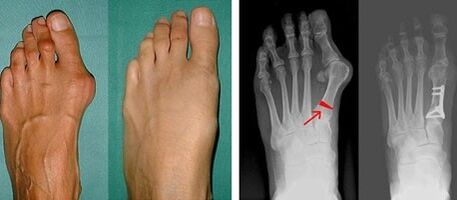

At the first stage of determining the valgus of the big toe and little toe, the doctor conducts a visual examination.In this way, it determines the stage of development of the pathology.To determine detailed changes in the joints, X-rays and phagocytography are prescribed.

If visual examination and X-rays show no findings, the patient will be referred for plantar fasciography to determine the possibility of flat feet.This method involves taking an impression of the foot, on the basis of which shoes or insoles with orthopedic properties are made for the patient.The patient is then prescribed podometry.This method uses computer analysis to determine the pressure of body weight on the foot.Advanced diagnostic results are the basis for choosing the first and second curvature of the toes treatment method.

The disadvantage of X-rays is that it requires radiation to the patient's legs, which many patients do not like.They think this is too harmful a method.In this regard, it is impossible to begin effective treatment of hallux valgus without the results of phalangeal imaging.